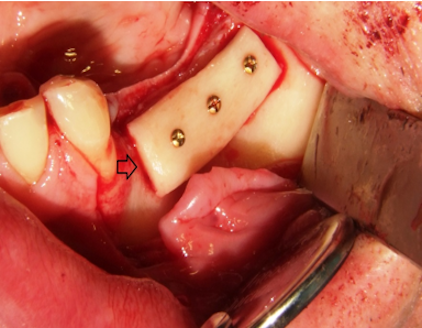

The block grafts were then fixed with 1.0 mm small-diameter titanium osteosynthesis screws. Additionally, bone chips, which were harvested by using a bone scraper at the donor site as well, were packed around the bone block to fill gaps between the block graft and the recipient bone (Figure 3 [Fig. 3]). Before wound closure with 4/0 resorbable sutures, the entire graft was covered by a collagen membrane (Bio-Gide, Geistlich Biomaterials, Wolhusen, Switzerland).

Figure 3: The bone graft is placed in the bone defect in the maxillary left posterior area and fixed with three titanium osteosynthesis screws (arrow).